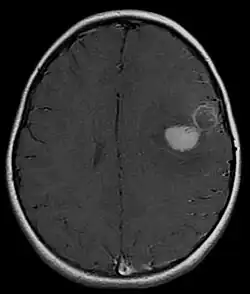

![]() RMN cerebral con contraste de PNETs en niña de 5 años afectando sobre área motora del habla (Broca) con sangrado intraparenquimatoso. | ||

- Resonancia magnética cerebral (RMN): la parte sólida es isointensa (misma intensidad) comparada con la corteza en el T2WI. Captación moderada de contraste. Se puede observar zonas hemorrágicas y quístcas. siembras en espacio subaracnoideo se suelen observar en el 36% de los pacientes. Reducción de la difusión en DWI. En la Espectroscopia es característico la disminución de NAA y aumento de colina y de lactato/lípido.